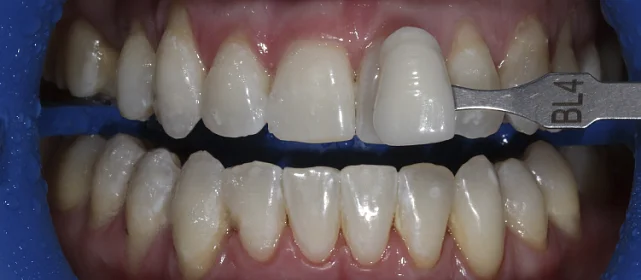

Нарушение соотношения челюстей и неправильное положение зубов — зубные ряды смыкались некорректно, зубы стояли со смещением.

Проблема: В клинику обратился мужчина с жалобами на неправильное положение зубов и смыкание — ряды сходились некорректно, зубы стояли со смещением. При этом было важно, чтобы лечение оставалось незаметным для окружающих, поэтому вариант с брекетами не рассматривался.